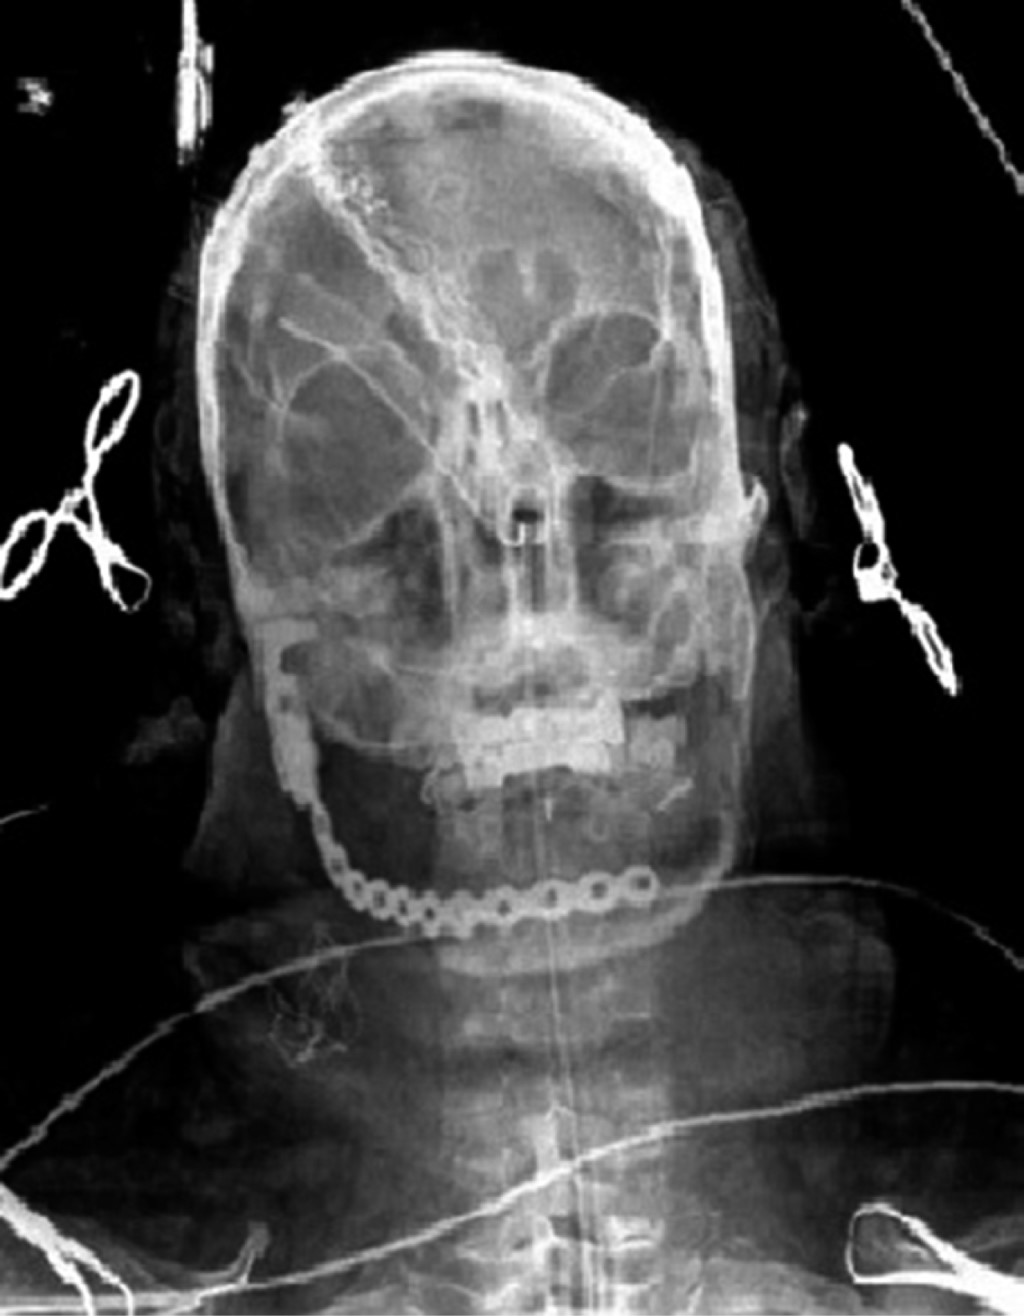

Inició padecimiento 19 meses previo a su primera valoración refiriendo chasquido súbito tras apertura máxima de la cavidad bucal, presentando dolor y aumento de volumen en la región posterior de la mandíbula derecha. En ortopantomografía se observa una zona radiolúcida, multilocular que abarca la rama ascendente derecha de la mandíbula y porción posterior del cuerpo mandibular con desplazamiento de tercer molar hacia borde cervical mandibular (Figura 1). En tomografía computarizada se observa lesión patológica multilocular que abarca la rama ascendente de la mandíbula, apófisis coronoides y hasta el cuello del cóndilo, la de mayor diámetro es de 35 × 32 mm con perforación de corticales casi en su totalidad y expansión de las corticales residuales (Figura 2). Se procede a realizar toma de biopsia incisional con un resultado de ameloblastoma folicular con datos de atipia celular (Figura 3), por lo que se decide solicitar gammagrama óseo que muestra una captación anormal en la rama mandibular derecha desde el cóndilo que correlacionan con la tumoración presente, así como un resultado negativo a la extensión metastásica ósea (Figura 4). Se decide realizar hemimandibulectomía y colocación de placa de reconstrucción con componente condilar. Se solicita estereolitografía para la preconformación de la placa de titanio y así disminuir el tiempo transoperatorio y márgenes de error en su colocación (Figura 5). Bajo anestesia general balanceada (AGB) se realizó fijación intermaxilar con ayuda de tornillos y cadena elástica. Se hizo incisión submandibular, se diseco el tejido por planos hasta llegar al hueso mandibular, se procedió a realizar hemimandibulectomía derecha, posteriormente se colocó placa de reconstrucción (Medartis MODUS®) con bloqueo y dispositivo condilar para reconstruir el cuerpo y rama mandibular (Figura 6), se verificó la oclusión, y el ajuste de la placa mediante toma de radiografía de control transoperatoria (Figura 7), se suturó por planos con sutura Vycril 3.0 y Polipropileno 5-0 para confrontar tejidos. El postoperatorio cursa sin complicaciones, por lo que se decide su egreso hospitalario para continuar su tratamiento por consulta externa en servicio de cirugía maxilofacial (Figura 8). El resultado histopatológico de la muestra completa reporta un espécimen formado por islas y cordones de epitelio ameloblástico de aspecto folicular y acantomatoso y displasia leve en un tejido conectivo fibroso denso bien vascularizado. Dos años después del procedimiento quirúrgico el paciente se encuentra asintomático y sin datos clínicos o radiográficos de recidiva.

Figura 1